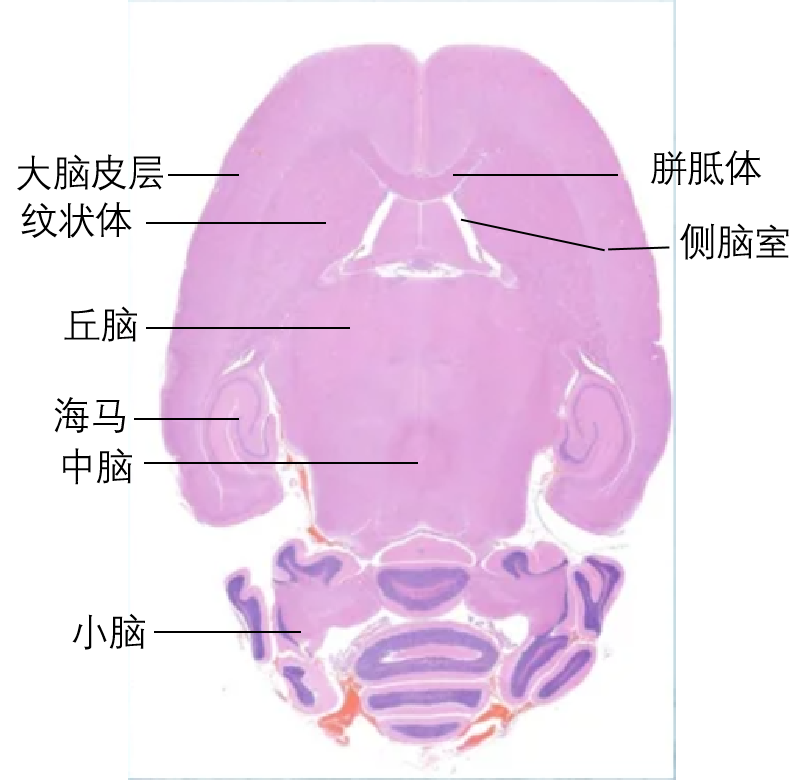

二、脑组织切面

脑组织的切面多种多样,最常用的有冠状面(coronal)、矢状面(sagittal)和水平面(horizontal)。

| 冠状切面(将脑分为前后两半):常见切面:前额叶皮层、纹状体 、小海马(经典海马)、大海马(黑质) | 矢状切面(将脑分为左右两半):可同时观察嗅球,皮层,纹状体,海马,小脑等;适合同一标本做不同实验左右对照 |

水平切面(将脑分为上下两半):可同时观察皮质、纹状体、海马、中脑、小脑等;看病理分布推荐水平切面 |